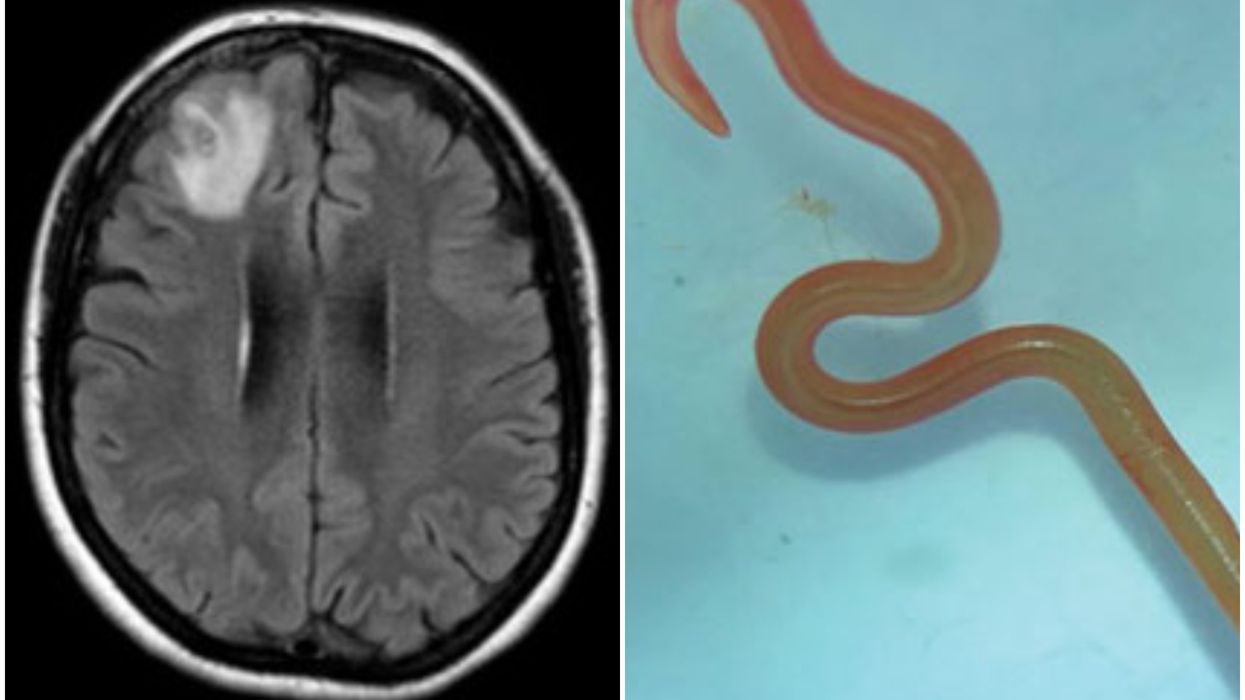

A brain scan of the patient and the 'wriggling, live worm'

Doctors in Canberra, Australia, were left stunned after they pulled the 8cm (3in) parasite from the patient’s damaged frontal lobe tissue during surgery last year.

"Everyone [in] that operating theatre got the shock of their life when [the surgeon] took some forceps to pick up an abnormality and the abnormality turned out to be a wriggling, live 8cm light red worm," said infectious diseases doctor Sanjaya Senanayake, according to the BBC.